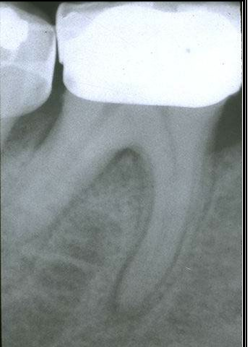

root anatomy

-palatogingival groove

-root trunk length

-root proximity

-root groove

root trunk length

-distance from CEJ to opening of furcation

-shorter means less distance to travel = get to furcation entrance sooner

-difficult to treat area